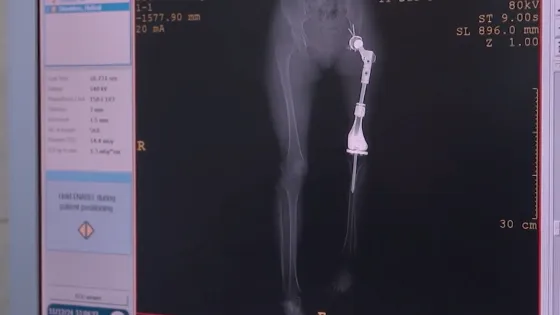

- В РФ создан первый в мире детский раздвижной эндопротез голеностопного сустава.

- Разработка была успешно установлена пятилетней девочке.

- Уникальный эндопротез был успешно установлен в НМИЦ онкологии им. Н. Н. Блохина.